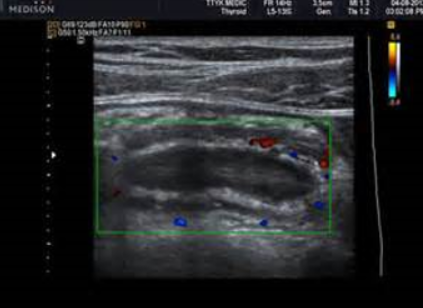

Crohn’s Disease